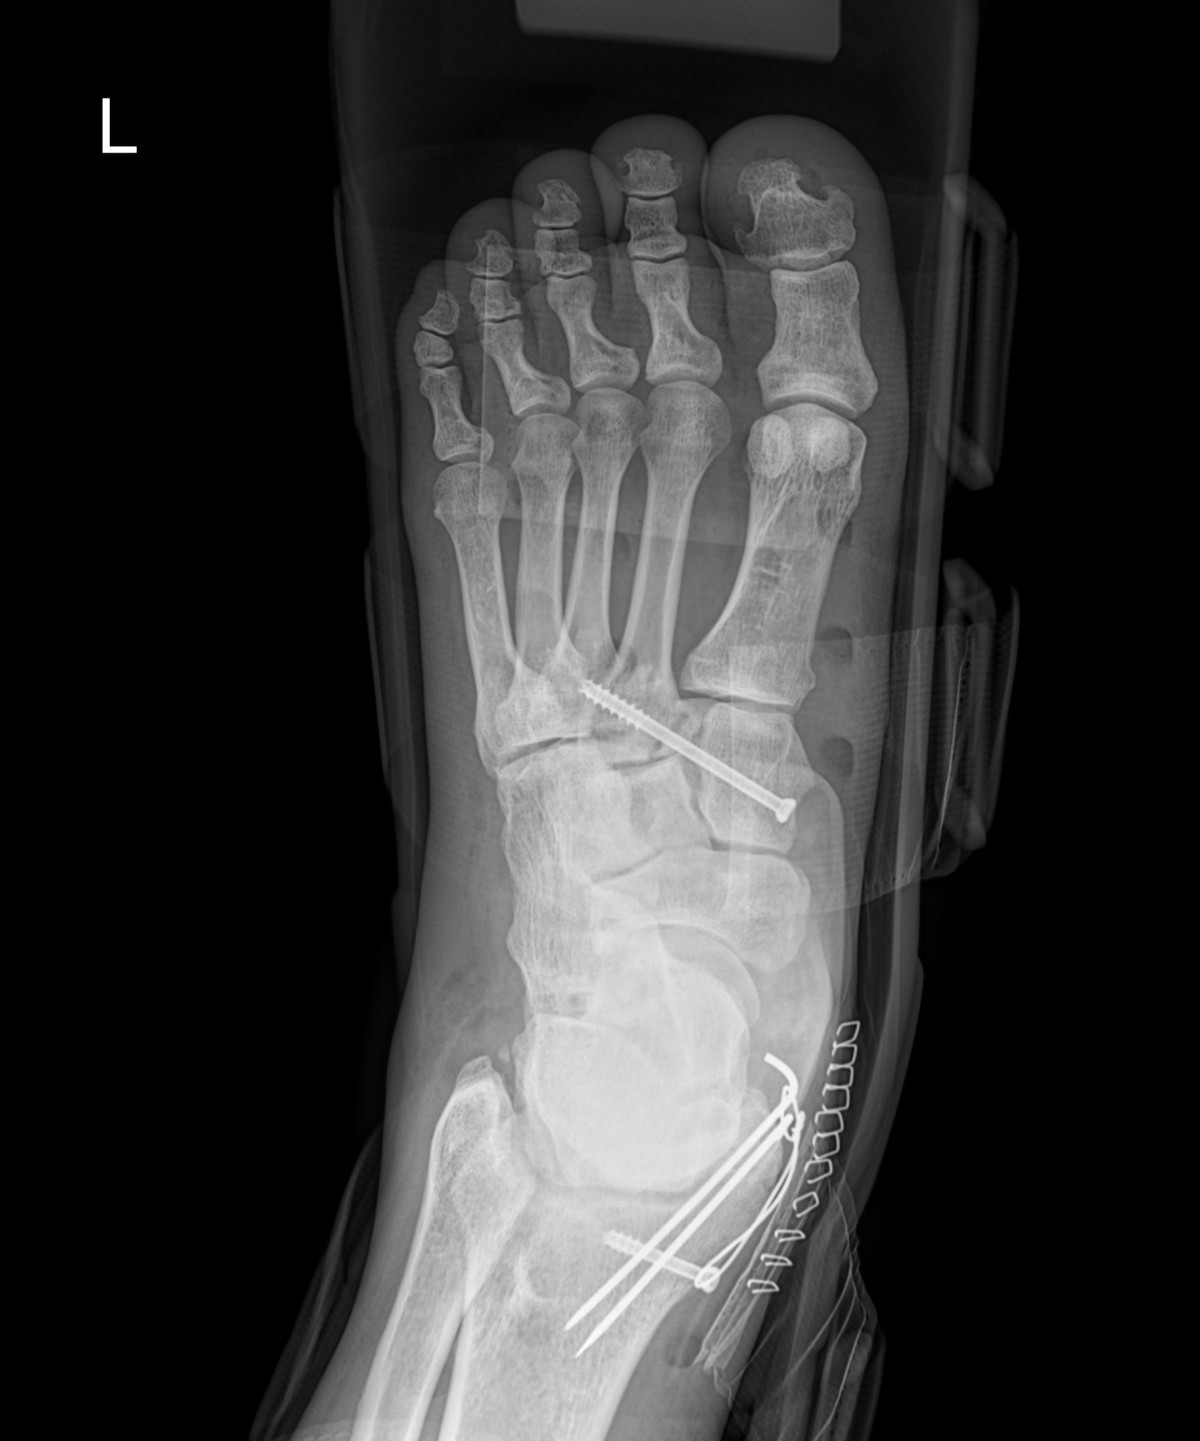

이재상원장님 발등 골절 수술 유현O 환자

dae765e4d9ac96aee867c9d6292d8784_1758003332_3532.jpg